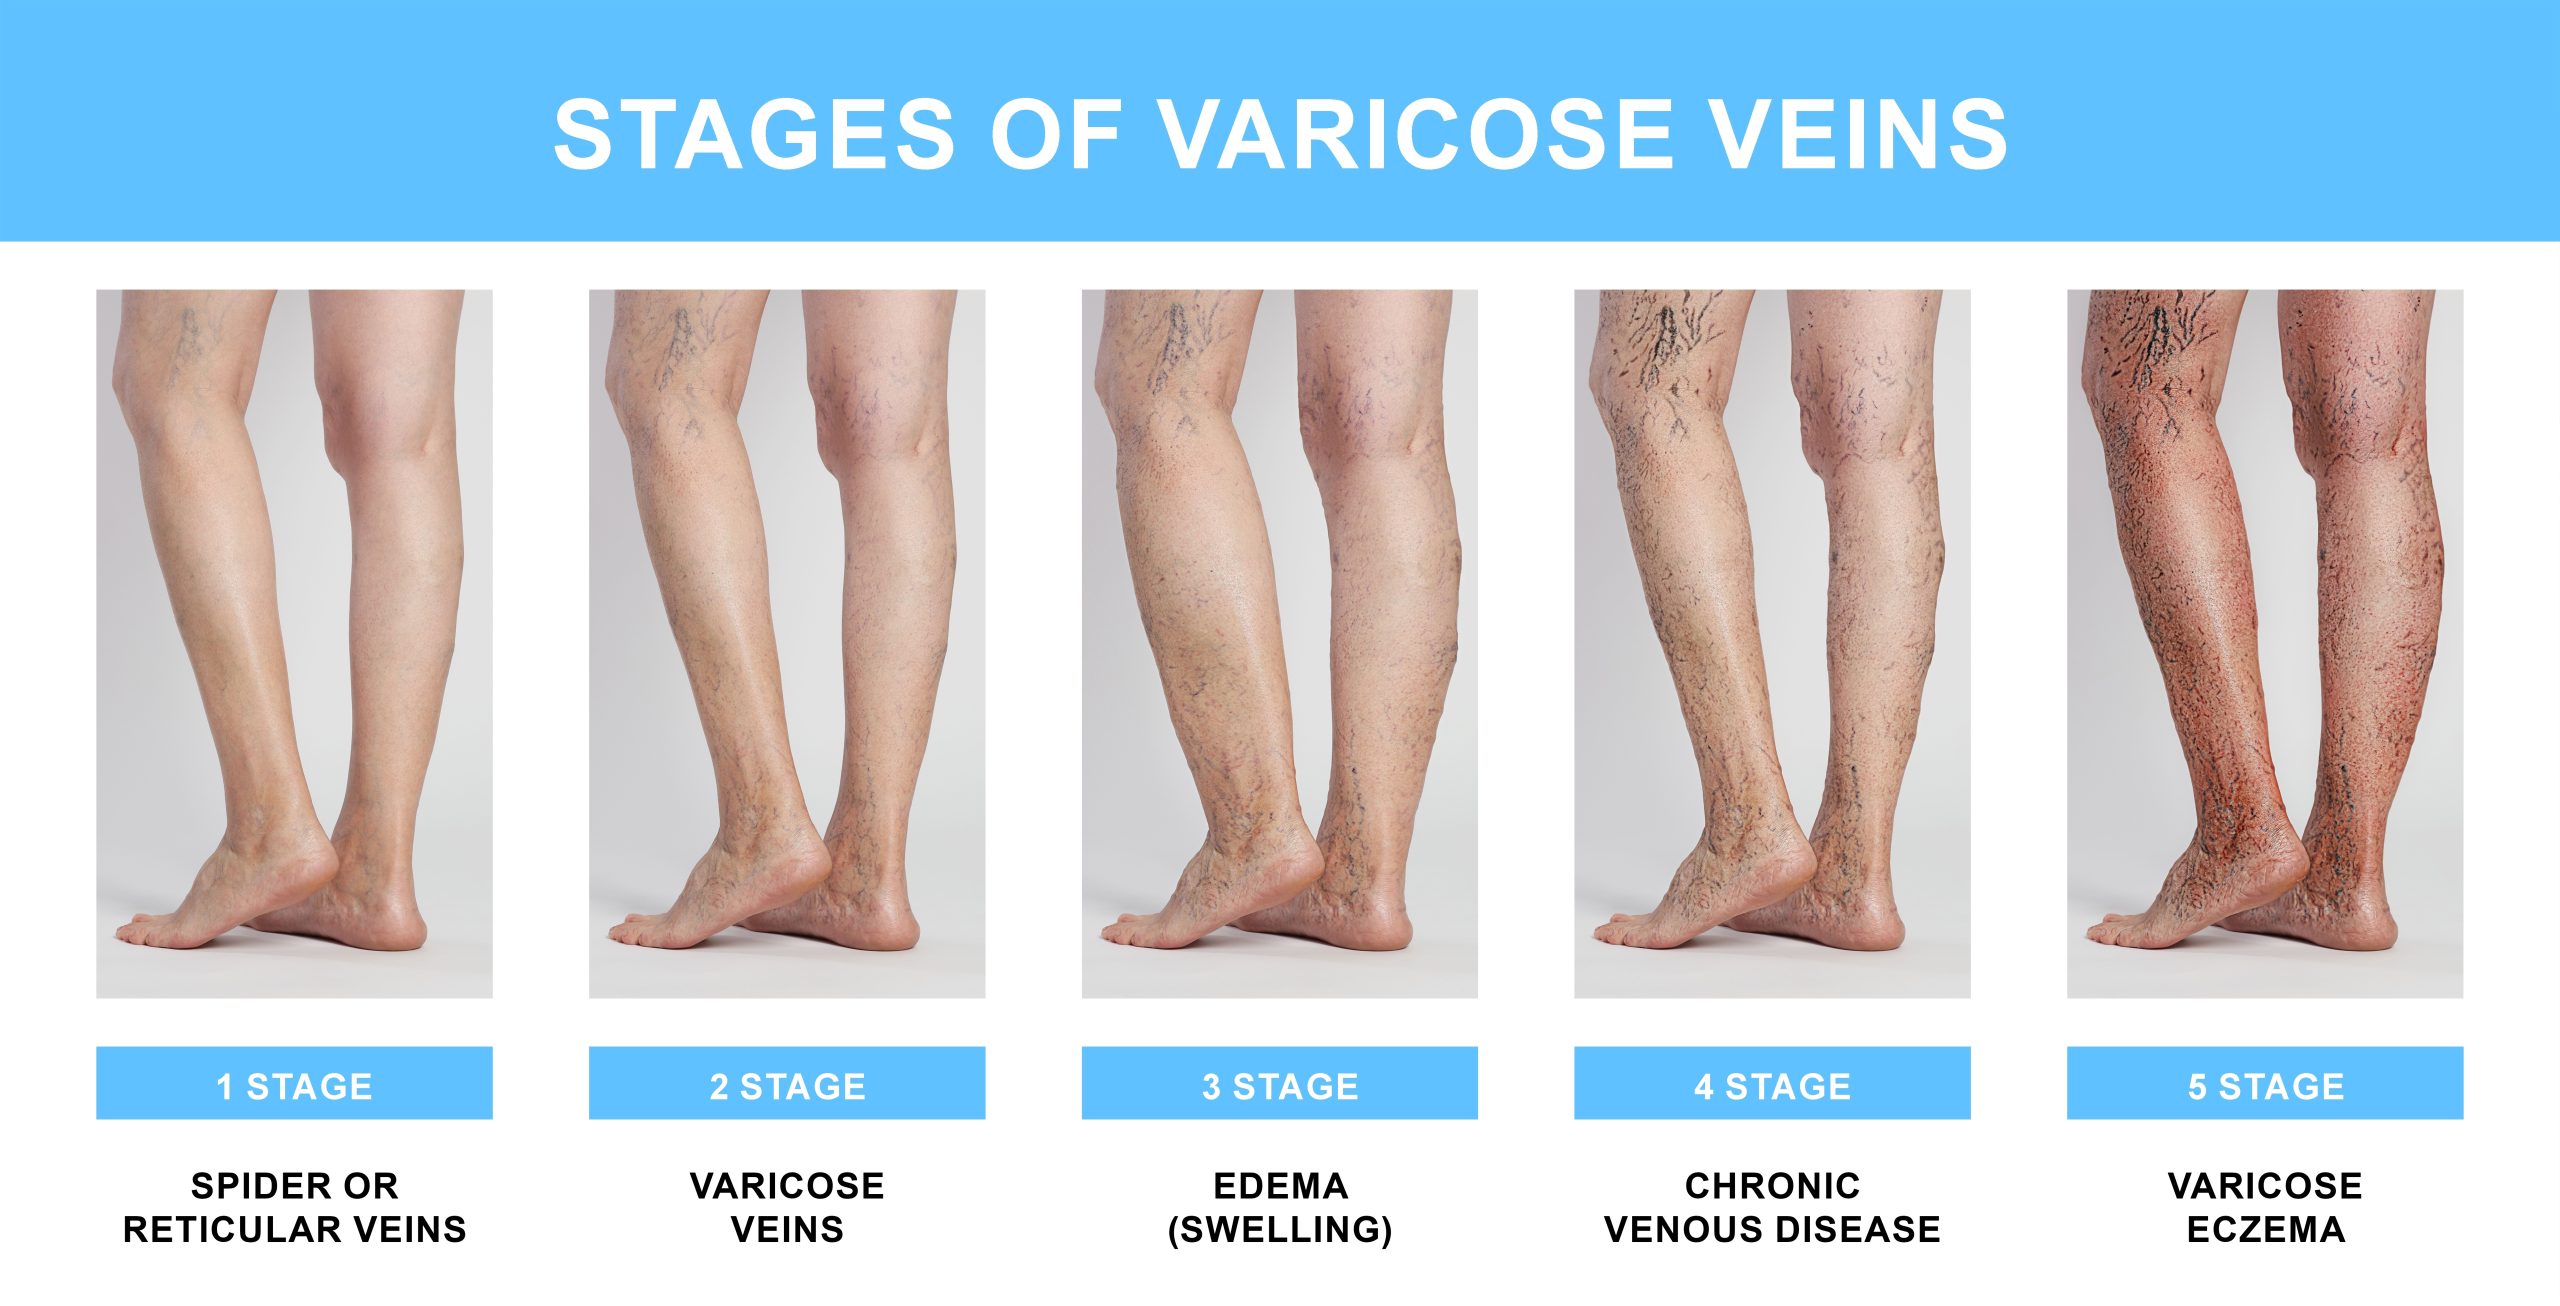

When you ignore varicose veins, they can burst and bleed. Read this article to know about hidden dangers…

When you google “Stages of Varicose Veins” or ask doctors or other people, you will get different answers…